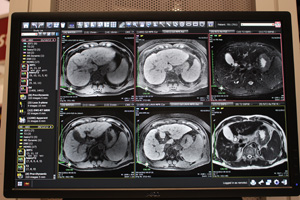

放射線科医の読影負担軽減をめざして開発されたAZE Phoenixは,リリース後も進化を続けており,RSNA 2013では,新しい機能として,“バーチャルシリーズ”を紹介した。これは,特に多くのシリーズの画像比較が必要になるMRI画像の読影において有用性を発揮する機能で,画像上でスクロールするだけで,次々とシリーズを切り替えることができる。画面を分割したコマにT1やT2などシーケンスごとに画像を振り分けて,それぞれを連続的に読影したり,たとえば検査当日のデータをすべてインストールし,1画面ですべてのシリーズを連続で読影するといったことが可能になる。これにより,日常の読影業務のさらなる効率化,負担軽減を図ることができる。シリーズの順番などは自由に設定でき,Webブラウザのユーザーインターフェイスのように直感的な操作性で,ストレスなく読影を行うことができる。また,シリーズや撮影日が異なる画像を高い精度で位置合わせ可能なボリュームレジストレーション機能を適用することもできる。

また,AZE Phoenixは,一般的にPACSに搭載されている心胸郭比計測や,RECIST計測機能などの計測機能も充実させ,PACSビューアとして使用することも視野に入れたシステムとなっている。RECIST計測機能では,計測結果をレポートに貼りつけることができるだけでなく,レポートからPhoenix内のデータを検索することもできる。

AZE Phoenixの読影画面

RECIST計測機能 |

バーチャルシリーズの1画面表示 |